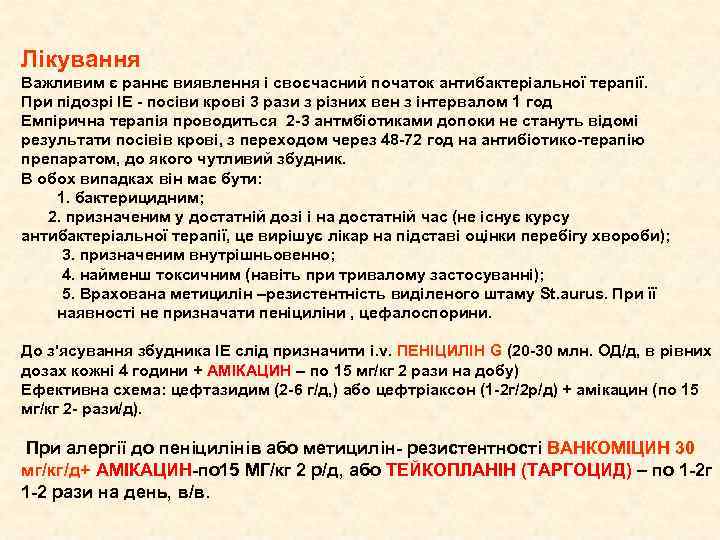

Лікування Важливим є раннє виявлення і своєчасний початок антибактеріальної терапії. При підозрі ІЕ - посіви крові 3 рази з різних вен з інтервалом 1 год Емпірична терапія проводиться 2 -3 антмбіотиками допоки не стануть відомі результати посівів крові, з переходом через 48 -72 год на антибіотико-терапію препаратом, до якого чутливий збудник. В обох випадках він має бути: 1. бактерицидним; 2. призначеним у достатній дозі і на достатній час (не існує курсу антибактеріальної терапії, це вирішує лікар на підставі оцінки перебігу хвороби); 3. призначеним внутрішньовенно; 4. найменш токсичним (навіть при тривалому застосуванні); 5. Врахована метицилін –резистентність виділеного штаму St. aurus. При її наявності не призначати пеніциліни , цефалоспорини. До з'ясування збудника ІЕ слід призначити і. v. ПЕНІЦИЛІН G (20 -30 млн. ОД/д, в рівних дозах кожні 4 години + АМІКАЦИН – по 15 мг/кг 2 рази на добу) Ефективна схема: цефтазидим (2 -6 г/д, ) або цефтріаксон (1 -2 г/2 р/д) + амікацин (по 15 мг/кг 2 - рази/д). При алергії до пеніцилінів або метицилін- резистентності ВАНКОМІЦИН 30 мг/кг/д+ АМІКАЦИН-по 15 МГ/кг 2 р/д, або ТЕЙКОПЛАНІН (ТАРГОЦИД) – по 1 -2 г 1 -2 рази на день, в/в.